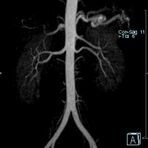

Aorta

• Bauchgefäße

• Erfassung und Verlaufskontrolle bei arteriellen Aneurysmen (Aussackungen der Arterien), vor allem der Bauchaorta

• Darstellung von Gefäßengen an Nierenarterien, Baucharterien und Becken-/Beinarterien

MR-Angiografie (MRA)

Ganzkörper Angiographie mit Kontrastmittel

• MR-Angiographie mit Kontrastmittel

• Erfassung arterieller und venöser Gefäße/Bypässe aller Körperregionen mit 3D-Rekonstruktion

• je nach klinischer Fragestellung zeitaufgelöste MR-Angiographie (4D-MRA) z.B. bei Frage arteriovenöse Fistel/ Shunt oder Darstellung Unterschenkelarterien vor geplanter Bypassoperation.